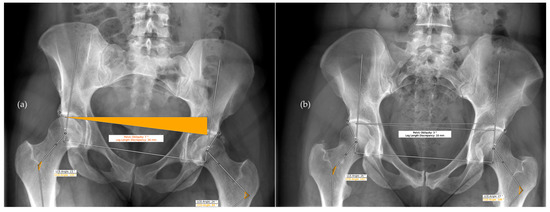

| Archer et al., 2022 [14] | Detection of Hip dysplasia through lateral CE, CCD, pelvic obliquity, Tönnis angle, Sharp angle, femoral head coverage using HIPPO™ | HIPPO™ used for Identification of bony landmarks. 256 ap hip radiographs for testing. Compared to three medical students who underwent instructions form one senior radiologist. | ICC for lateral CE: 0.71–0.86, for CCD: 0.62–0.79, for pelvic obliquity: 0.83–0.98, for Tönnis angle: 0.82–0.90, for Sharp angle: 0.74–0.86, for femoral head coverage: 0.5–0.73. |